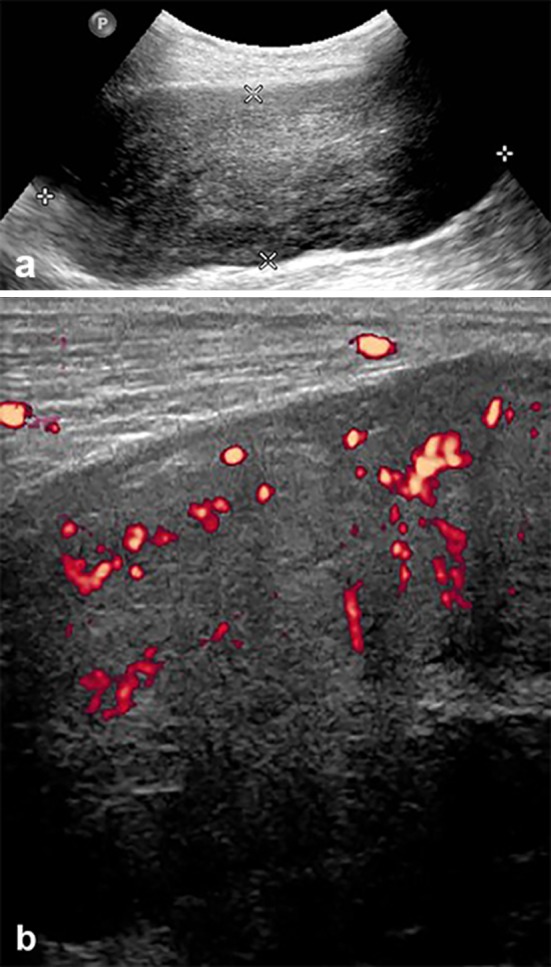

The patient is a 74-year-old man, known to have hypertension, coronary artery disease, diabetes mellitus and atrial fibrillation with prior left pelvic renal transplantation for renal failure. Post transplantation, the patient was maintained on daily cyclosporine, 100 mg orally in the morning and 75 mg orally in the evening, and prednisone 5 mg orally once daily. Thirteen years later, he presented with painless hematuria of 5 months duration and was found to have a renal mass on ultrasound and CT scan located at the upper pole of the left native kidney for which left nephrectomy was performed and revealed renal cell carcinoma on tissue diagnosis. One year later, right native nephrectomy was done after detecting another renal mass at the lower pole of the right kidney during regular CT follow-up. No chemotherapy was administered after both nephrectomies, since both metachronous renal cell carcinoma were localized. Three years later the patient presented with a large palpable posterior left leg mass. Ultrasound showed a 10.6 × 3.9 × 5.7 cm, slightly heterogeneous, hypoechoic mass in the posterolateral aspect of the left calf, located within the medial aspect of the soleus muscle (Fig. 1a). It showed increased vascularity on power Doppler examination (Fig. 1b).

Fig. 1.

Grayscale ultrasound image of the left calf (a) showing large lobulated slightly heterogeneous soft tissue mass. Power Doppler exam (b) revealed significant increased flow within the tumor